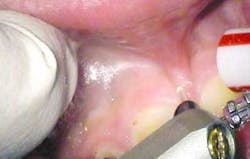

Once the Erbium part of the procedure is completed, the Superpulsed CO2 (OpusDuo, Opusdent USA) is then used to simply coagulate and gently cauterize the bleeding site. With this approach, the practitioner can immediately pick up a focused 90-degree handpiece and apply 1.5 watts in the Superpulsed noncontact mode. This is accomplished with a circular sweeping pattern to gently coagulate the superficial bleeding layer to a depth of 75-100 microns (figures 6 and 7).